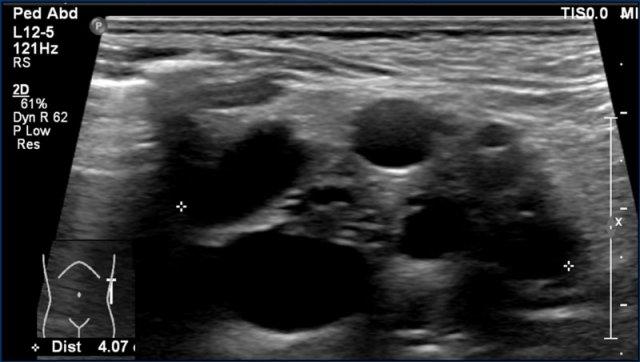

Đây là bé trai hai tuổi mắc hội chứng Beckwith-Wiedemann.

Siêu âm sàng lọc phát hiện một khối u nhỏ đồng nhất ở phần thận trái của thận móng ngựa.